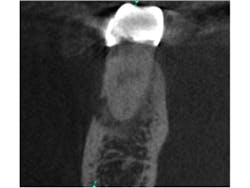

Fig. 2 is a sagittal slice through the lesion, further showing the mixed nature of the lesion. Figs. 3 and 4 are coronal and axial slices respectively. Both coronal and axial slices show that the PDL is intact around the root end and show that the lesion has caused erosion of the buccal cortical plate. Due to the unusual appearance of this lesion, an oral and maxillofacial radiologist also evaluated the CBCT scan.

Fig. 3: Coronal slice through the mesial root of tooth No. 30. Note the PDL being undisturbed around the apex and the erosion of the buccal cortical plate.